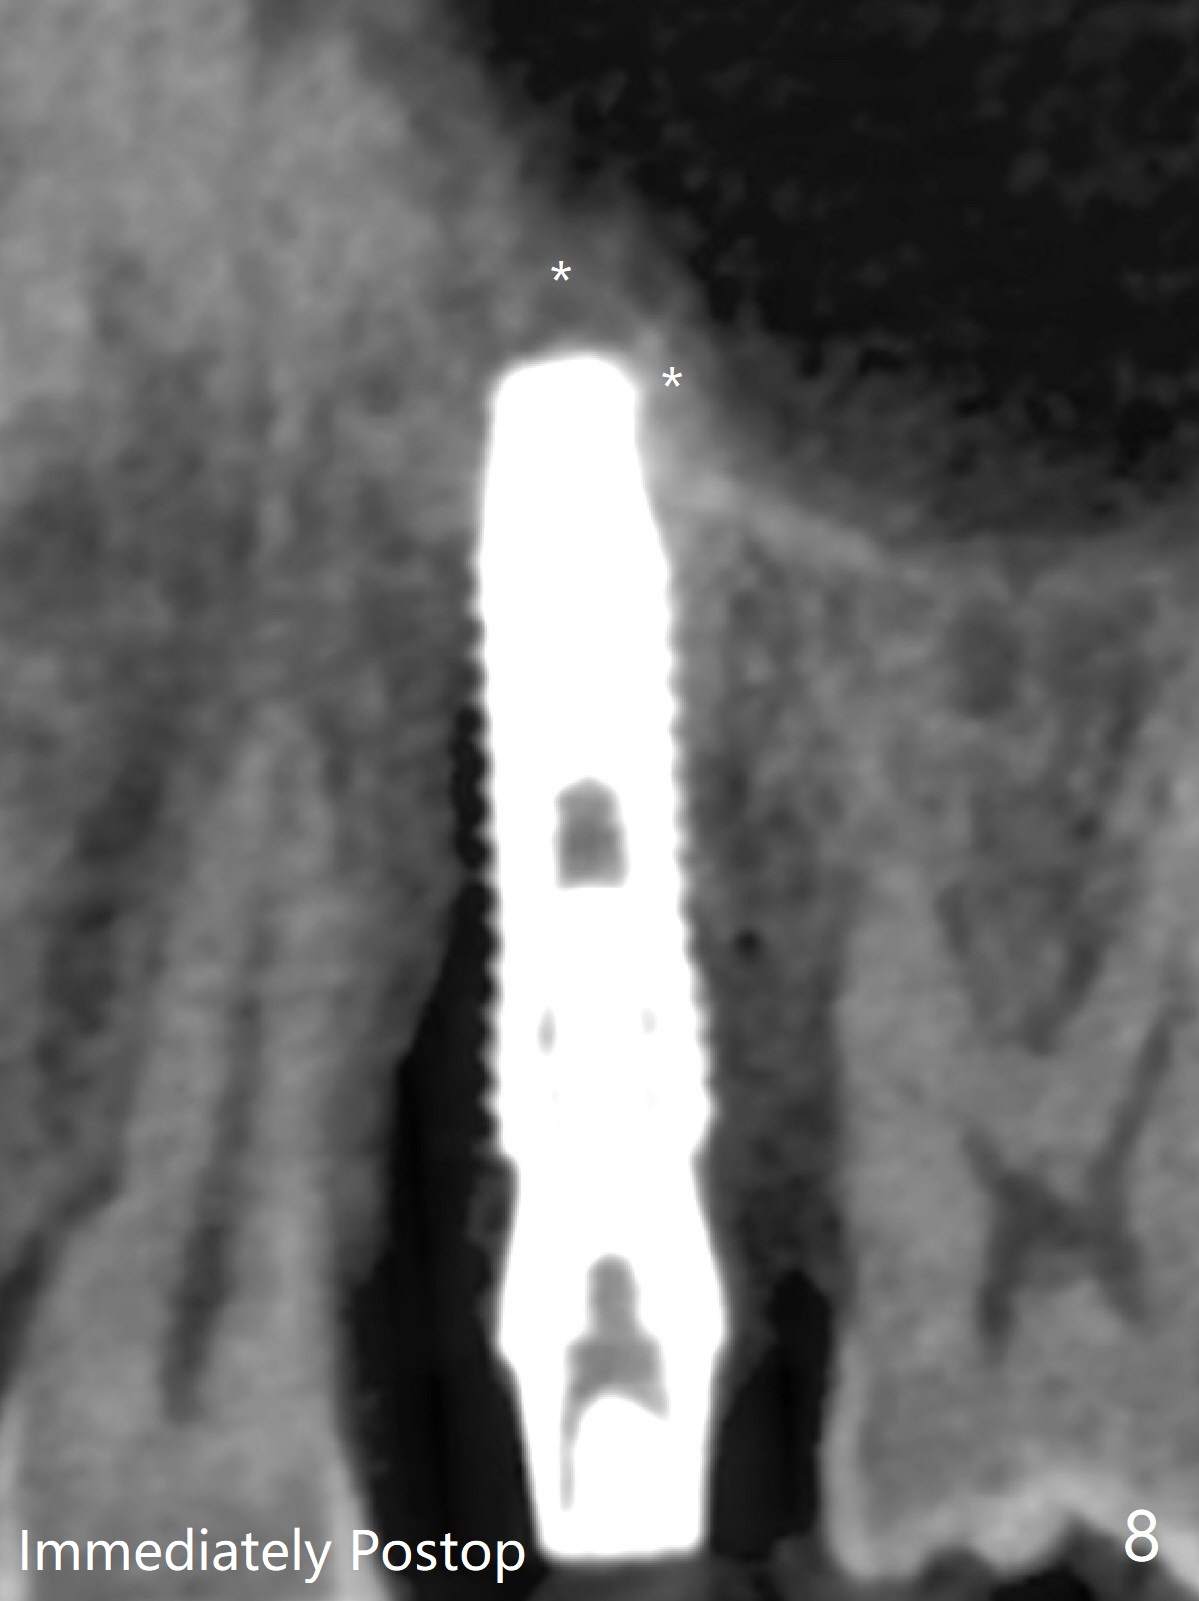

DIO lab refuses fabricating guide because of the large socket and recommends extraction and socket preservation at #13. Due to short apical bone (Fig.5,7), a long dummy implant (3.8x15 mm) is placed with periimplant space immediately post extraction (Fig.1 *). The final implant is larger (4.5x15 mm) with simultaneous sinus lift and periimplant bone graft (Fig.2,6,8 *). To repair the palatal crest defect (Fig.3 *) associated with tooth fracture (Fig.5 white dashed line), the implant is not placed too palatal with sufficient amount of the bone graft (Fig.4,6 *). The native bone (higher in bone density, Fig.9 white arrowheads, as compared to black one (for bone graft)) appears to have grown into the space between implant threads 5.5 months postop. The permanent crown/abutment is loose 1 year 9 months post cementation; after proximal reduction (Fig.10 arrowheads), the abutment is reseated completely. Pick up impression is taken and a healing abutment is placed. A few days later, the crown and abutment (separate) are seated passively; the abutment screw is retightened; the crown is re-cemented. The crown and abutment is removed for residual cement removal (Fig.11). Since there is mild buccal plate atrophy (Fig.11 B), the crown has a buccal lip (Fig.12 B) to prevent food impaction. The lip makes it difficult to remove residual cement intraorally. Therefore an access hole is necessary (Fig.13).